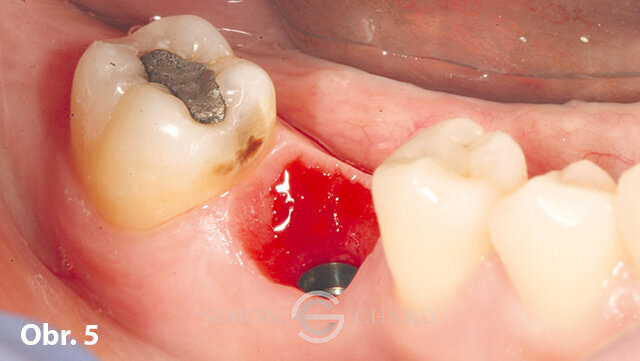

Po 3měsíční vhojovací fázi se pacient dostavil zpět pro osazení implantátu definitivní korunkou. V průběhu této doby měly měkké tkáně okolo implantátu prostor se formovat, díky čemuž kolem něj vytvořily krásný tvar (obr. 4, 5).

Obvykle při použití metod s analogy je právě detailní zachycení profilu měkké tkáně okolo implantátu komplikované a časově náročné. Nicméně, při použití digitálního intraorálního skenování (CEREC Omnicam) můžeme využít „skenu gingivální masky“ k přesné replikaci měkkých tkání a k modelaci emergence profile výsledné korunky (obr. 6).

Po sejmutí provizorní korunky byla na implantát dosazena TiBase se skenovacím tělískem tvořícím referenční bod pro sken implantátu.